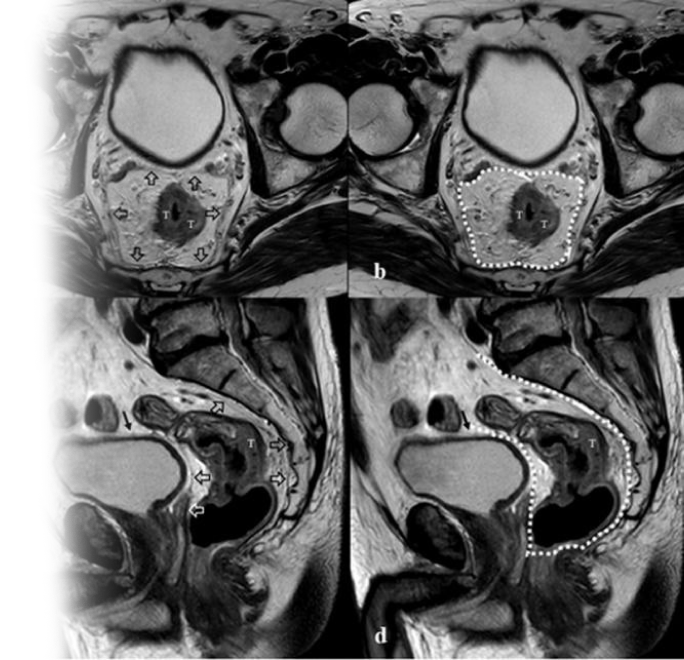

Магнитно-резонансная томография органов малого таза с прицельным описанием анального канала – важный метод исследования с введением контрастного вещества, который позволяет визуализировать предстательную железу, семенные пузырьки, мочевой пузырь, перианальную область.